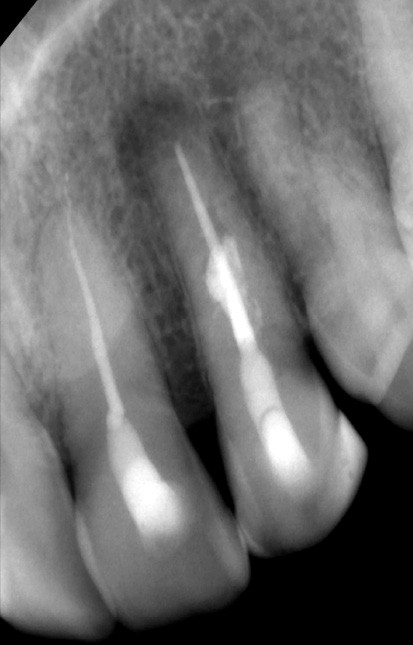

Si l’étude de Peters [18] nous montre que l’instrumentation laisse 35 % du volume canalaire non instrumenté, Ricucci et Siqueira montrent que la préparation physico-chimique n’élimine que partiellement les tissus nécrotiques à l’entrée des canaux latéraux, des isthmes et des ramifications apicales, en laissant des tissus enflammés et infectés, en association avec des lésions apicales [29] (fig. 4 et 5).

Fig. 4 – Coupe d’une racine mésiale de molaire mandibulaire avec deux canaux traités. Coupe à 3 mm de l’apex, coloration Brown et Brenn, technique modifiée par Taylor. Ces images montrent un isthme étroit avec une infection bactérienne, ce qui prouve l’importance de désinfecter et d’inclure l’isthme dans les traitements conventionnels et dans les rétropréparations apicales en chirurgie endodontique.